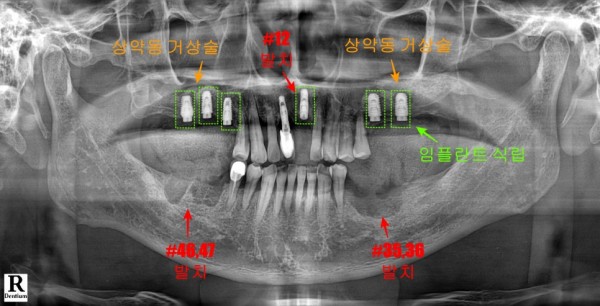

첫 번째 치료 단계에서는 무엇보다 시급한 문제부터 해결하기로 했습니다.

염증이 심하게 진행된 앞니 한 개와 아래쪽 어금니 네 개를 발치하는 것부터 시작했습니다.

발치와 동시에 위쪽 어금니 부분에 임플란트를 식립하여

환자분이 가능한 빠른 시일 내에 저작 기능을 회복할 수 있도록 했습니다.

이때 임플란트 위치 선정과 각도 조절을 위해

사전에 디지털장비를 이용해 계획했는데요.

이러한 작업을 통해 수술 시간도 단축되고

환자분의 부담도 줄일 수 있습니다.

또한 양쪽 어금니 부분의 부족한 치조골 상태를

개선하기 위한 상악동거상술도 함께 진행했습니다.